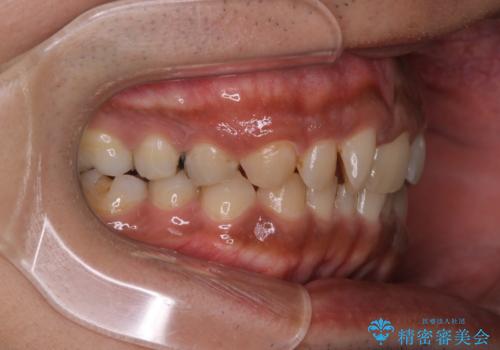

【モニター】インビザライン 前歯の捻れを治したい

- 30代男性

- 矯正装置

- インビザライン

- 治療期間

- 1年6ヶ月

- 治療計画

- 上下の前歯のがたつきを主訴に来院されました。インビザラインで治療可能と判断致しましたので、IPR(歯と歯の間を削る処置)と歯列弓拡大をして

がたつきをとる治療計画を立てました。

マウスピースをしっかり使用していただいたことで、主訴である前歯のがたつきも改善され

リファイメントも1回のみで治療を終了することが出来ました。